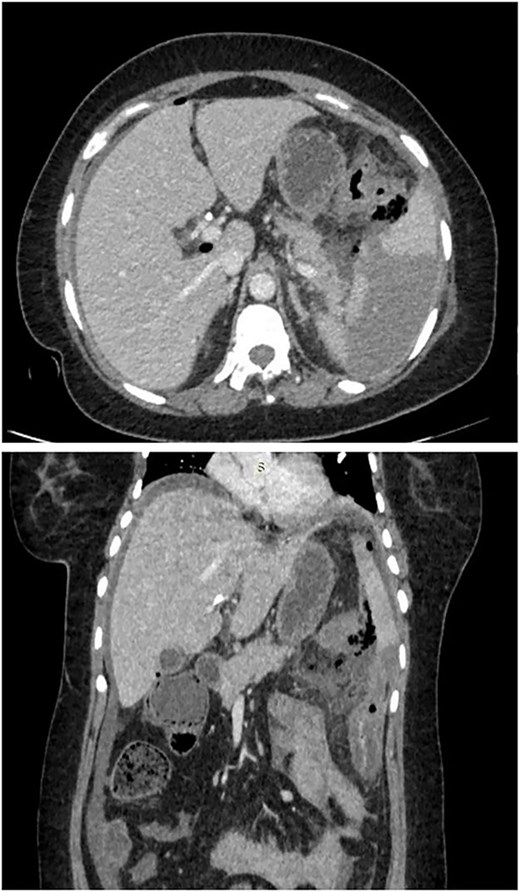

Patient was taken for emergency laparotomy which showed ~200 ml of pancreatic free fluid with purulent and feculent material, calcified pancreas with dense adhesions, 2 × 1 cm perforation in splenic flexure of colon as shown in Fig. 2. Resection and anastomosis of splenic flexure of colon with proximal loop ileostomy with placement of 2 abdominal drain was done. Patient was shifted to intensive care unit for post op care.

2 × 1 cm splenic flexure of colon perforation & necrotic pancreas.